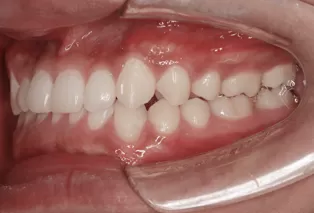

Photos intra-orales